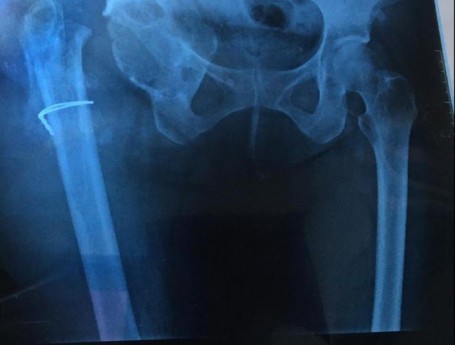

Revision Total Hip Arthroplasty